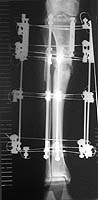

I am a 55-year-old male who suffered a compound fracture of the right tibia and fibula and extensive soft tissue damage, including vascular damage, from the impact of an automobile pinning the leg to a concrete wall in 1971. This occurred while I was a pedestrian. Emergency surgery restored circulation and set the tibia and fibula fragments with no internal fixation (due to concern about infection) and plaster cast immobilization. Later a bone graft was performed, and after physical therapy an apparently full recovery occurred, except a slight varus deformity, reduced vascularity, and reduced range of motion in the ankle. Over the years, the varus deformity worsened to 22 degrees and led to moderate osteoarthritis. To correct the deformity and straighten the tibia, an open-wedge osteotomy was performed in November 1999, with a bone graft from the other iliac crest. Plate fixation was used, as the bone was too hard to ream, so it was impossible to insert a pin. I have used the Exogen ultra-sound device every day since the surgery. Gradual improvement led to enhanced weight-bearing ability, and I have been walking with a cane since April 2000. Although X-rays taken June 16 showed no deformity, the varus deformity has recurred in the October 16 X-rays.

I am interested in why this happened and what to do about it. Is a second osteotomy indicated? If so, is there a medical consensus on whether bone marrow implants promote osteogenesis? What about other implants of natural, artificial or combination materials? Are there any methods of reaming calcified bone for the purpose of pin insertion? Are there other remedies? Has anyone on the list seen varus deformities of the tibia recurring after an osteotomy? Would the Ilizarov device give better results within a reasonable time, taking into account age and impaired vascularity? And what other options exist that would straighten this thing out once and for all? I have copies of the June and October X-rays which can be sent as e-mail attachments off-list, and will be glad to answer questions insofar as possible.